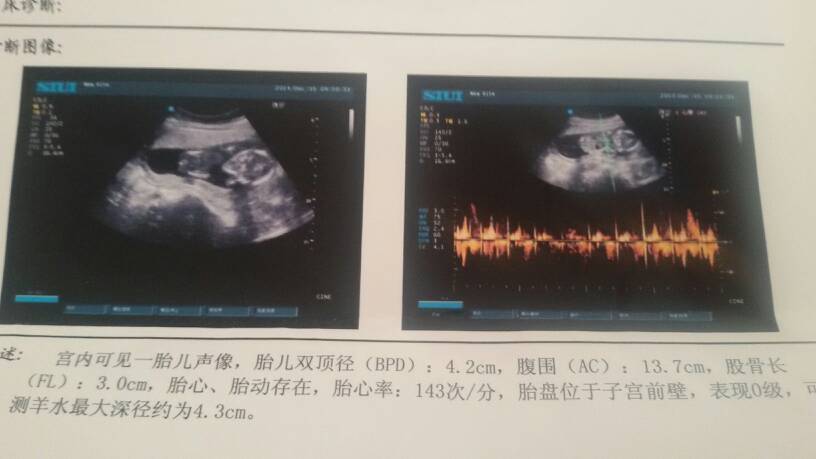

您好,你的情况考虑一般情况怀孕后14周进行B超检查是可以的,一般情况是可以判断男女孩的,一般情况80%是比较可靠的,不过怀孕后进行男女孩鉴别是违法的,一般情况医院是不允许鉴别的,估计私人医院是可以做的